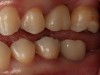

Plugging into digital workflows provides opportunities to integrate CAD/CAM technologies at every step of the treatment process for dental implants. In another example, a patient presented with a failing tooth No. 8 (Figure 6 and Figure 7). After discussing treatment options, the patient chose to forgo any treatment to address tooth and soft-tissue asymmetries and wanted to proceed with a dental implant-supported restoration without additional treatment. After integrated 3-dimensional planning, the tooth was extracted, and then an implant and the final custom CAD/CAM abutment (titanium base with zirconia supra-structure) were placed with a provisional restoration in the same visit (Figure 8 and Figure 9). Soft-tissue grafting was also done at the same visit to address the deficient buccal tissue height on No. 8 (Figure 10). At 3 months, the patient presented for the final restoration, with excellent healing around the implant (Figure 11) and soft-tissue healing guided by the custom abutment (Figure 12).

Fig 12. Clinical presentation of healed soft tissue and final custom abutment No. 8 placed on the day of the implant surgery 3 months prior.

Figure 12